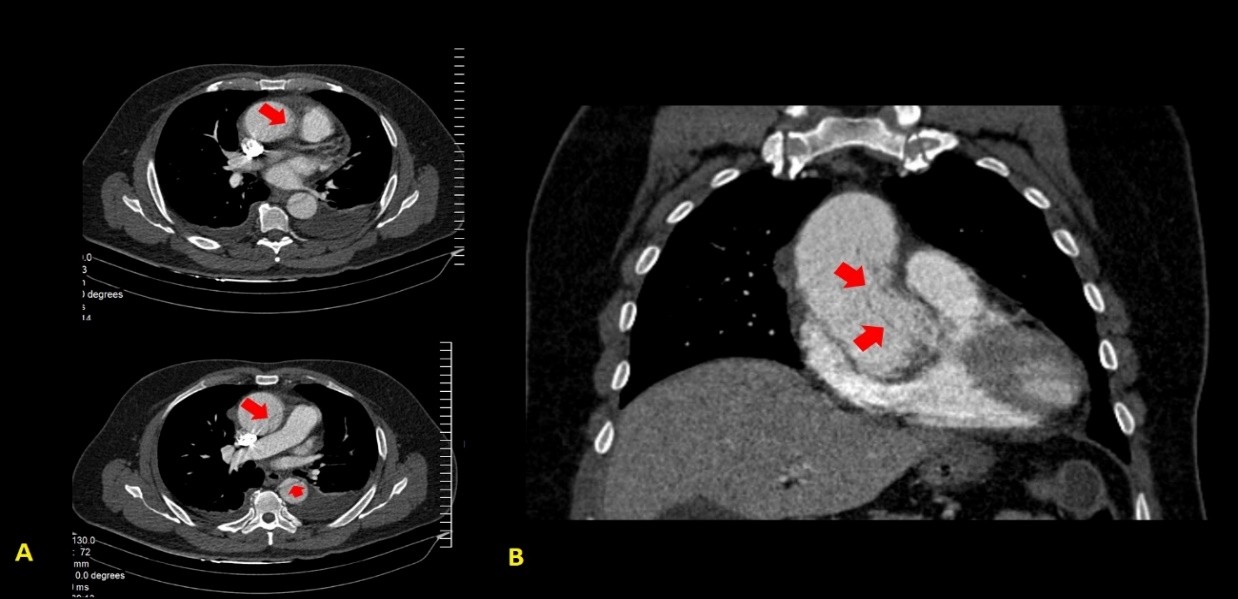

En la tomografía con cortes axial y coronal se observó el colgajo íntimo que dividía la luz aórtica en falsa y verdadera, aunque sin ocluirla. La disección comprometía la aorta ascendente, el arco aórtico, y aorta abdominal, y se extendía a las arterias renal derecha e ilíaca ipsilateral. Se constató derrame pericárdico leve (Fig. 2-4).

Fig. 2 - Tomografía axial computarizada de tórax. Cortes axial (A) y coronal (B). Obsérvese el colgajo íntimo (marcado con flechas rojas), concordante con la disección aórtica(I en la clasificación de DeBakey; A en la de Stanford).